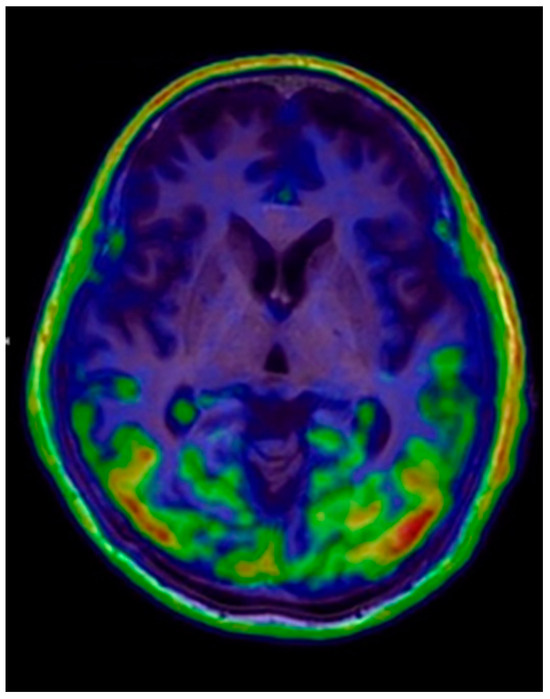

6.3. Tau PET

6.3.1. Imaging Data Display

6.3.2. Image Interpretation for Tau PET

Visual Analysis

Quantitative Analysis

- Techniques: Imaging is performed on an integrated 64-slice PET/CT scanner for the whole brain, with non contrast-enhanced CT for attenuation correction and localization in the transaxial, coronal, and sagittal planes. A 3D emission dynamic scan of the same area is acquired in a one-bed positionSemiquantitative calculations are performed using PMOD software with the automatic anatomical labeling (AAL)-merged atlas to generate automatic voxels of interest for different brain regions.

- Findings: Visual analysis: Describe abnormal tau deposition in the brain region.

- Interpretations/Impressions/Conclusions: Negative/positive studies should be mentioned when reporting the region of abnormal tau deposition.